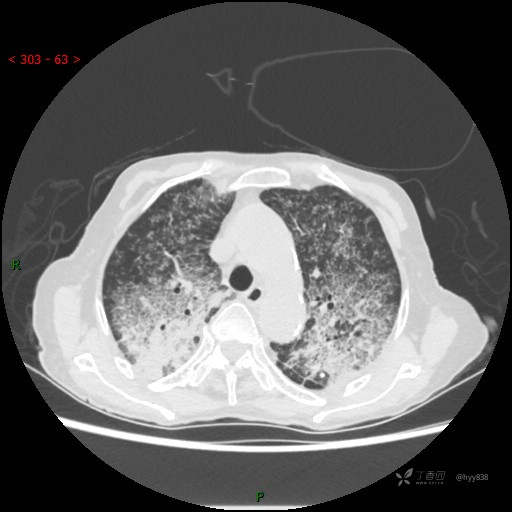

肺部弥漫性、疑难病变,感染或肿瘤?一元论或二元论?贴贴精彩---结果公布~

患者性别:女

患者年龄:73岁

主诉:反复发热10余天

简要病史:患者10余天劳累后出现发热,最高体温达39.5℃,无畏寒、寒战、鼻塞、流涕,无头晕、头痛,无心慌、胸闷、胸痛,无咳嗽、咳痰、气喘,无反酸、烧心、恶心呕吐,无腹痛、腹胀等不适,于2022-5-31至当地中医医院住院治疗,诊断为重症肺炎,予以抗感染、抗病毒等对症支持治疗,仍反复发热,现为求进一步诊治,至我院门诊就诊,门诊以“重症肺炎”收入我科。 起病以来,患者精神、饮食、睡眠差,大小便正常,体力下降,体重无明显变化。

临床诊断:重症肺炎

胸部CT平扫